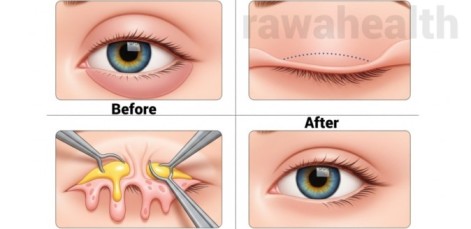

Eye Bag Surgery – Overview Eye bag surgery is a specialized cosmetic procedure designed to remove or reduce the appearance of under-eye bags and puffiness, giving a refreshed and youthful look. With aging, genetics, lifestyle factors, and fluid retention, many individuals develop noticeable eye bags that impact appearance and confidence. This guide provides an in-depth […]